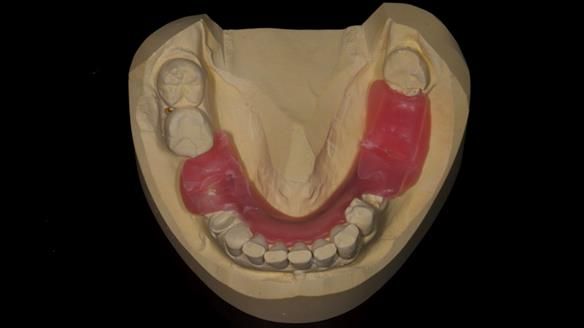

Keith’s combat denture case study

Keith’s case was one of the most challenging and rewarding cases I’ve treated this year. This 64 year old man presented with ill-fitting acrylic partial dentures that lacked stability, retention, and aesthetics. They constantly broke. He had lost the upper front teeth in a road traffic accident in his early 20s. The unopposed teeth had erupted, taking up space. After careful planning, we made a durable, metal-based upper partial denture/splint to address his dental concerns. He loved the outcome.

1. Denture design: A custom cobalt-chromium framework was Scandinavian-designed to maximise stability, protect the remaining teeth, and allow for future additions if needed.

3. Definitive alginate impression in custom tray: Used to ensure a well-fitting RPD.